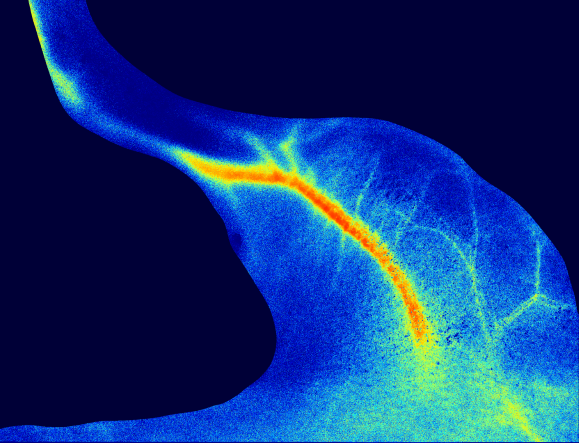

肠系膜血流灌注监测

小鼠肠系膜血流灌注成像